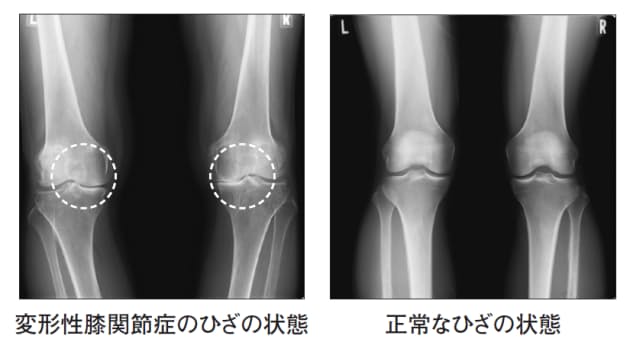

変形性膝関節症について かとう整形外科スポーツ運動器クリニック

変形性膝関節症 膝の周囲の筋肉を鍛え 肥満に気を付けましょう

変形性膝関節症 日本整形外科学会 症状 病気をしらべる

変形性膝関節症 整形外科 スポーツ診療科 順天堂医院

変形性膝関節症 年の膝 三島市医師会